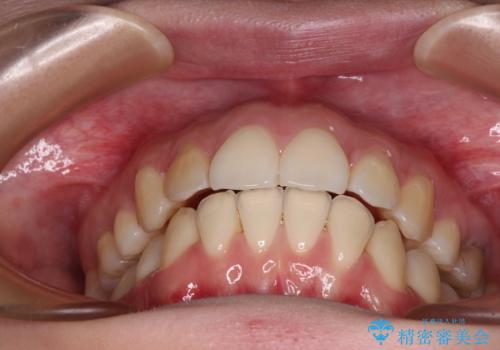

- 高校生の時に矯正治療を行ったものの、後取りをしてしまったとのことで来院された患者様です。

マウスピースでもワイヤー矯正でも対応可能でしたが、再度ワイヤーは装着したくないとのことでインビザラインにて矯正治療を行うこととしました。

舌の突出癖が原因で後戻りをしたため、舌のトレーニングをしっかりと行っていただき、口元の突出感を改善することができました。

インビザラインの装着時間が守れず、1年強で終わる予定でしたが、4年間を要することとなりました。